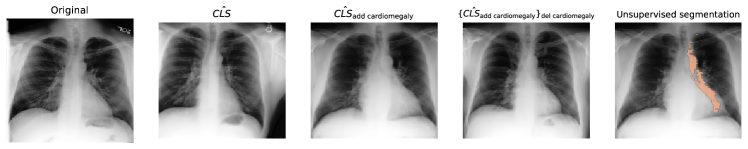

We evaluated the interpretability and validity of our SAE features using an experiment based on Monteiro et al. (2023)’s assessment of counterfactual imaging models—focusing on effectiveness, composability, and reversibility. SAE features are interpretable if they correspond to distinct concepts that respond predictably to activation space interventions. We trained a diffusion model conditioned on Rad-DINO class tokens (Pérez-García et al., 2024) to reconstruct MIMIC-CXR radiographs. During inference, we passed a class token through the SAE, intervened on encoder activations, and reconstructed a “counterfactual” token via the decoder, which conditioned the diffusion model to project interventions into imaging space. We tested whether: 1) interventions alter the reconstructed class token accordingly, 2) changes affect only the targeted feature, and 3) features can be “added” or “removed” by manipulating the same activation. Fig. 4 shows the results for two features (cardiomegaly and pacemaker), demonstrating that our interpretations accurately reflect their impact on model behavior. Further details are given in Appendix D.

Refer to caption

Figure 4: SAE-Rad enables counterfactual image generation and unsupervised segmentation with disentangled class tokens. Row 1 examines a pacemaker, and Row 2 investigates cardiomegaly. Column 1 shows original MIMIC-CXR images, Column 2 shows model reconstructions, and Columns 3 and 4 depict counterfactuals by adding and removing features. The final column demonstrates unsupervised segmentation by comparing counterfactual and original images. Details are in Appendix D.